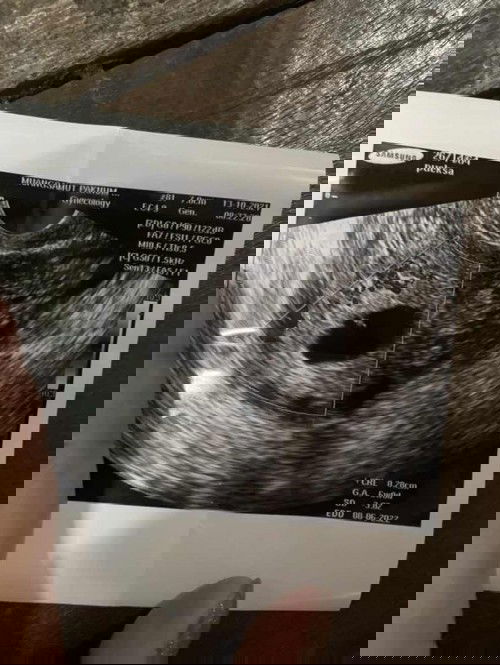

ท้องนี้ท้องที่ 4 แล้วค่ะ ถ้านับตามประจำเดือนหมด อายุครรภ์น่าจะ 9 วีคแล้ว เมื่อวานไปฝากครรภ์ หมอซาว แต่เห็นเป็นจุดเล็กๆ แลเวบอกว่าเด็กม่เจริญเติบโต นัดไปอีก 1 อาทิตย์ไปซาวดู ถ้าเด็กยังไม่โตขึ้นจะให้เรายุติการตั้งครรภ์ เราไม่อยากให้เป็นแบบนั้นเลย แต่เราท้องนี้เราแพ้มาก ทานอะไรไม่ได้เลย ข้าวก้อกินไม่ได้ หมอก้อไม่เห็นรับเราฝากครรภ์ เก็บเงินแต่ค่าซาวไป แล้วที่งงอีกอย่างทำไมในรูปซาวขึ้นแค่ 6 วีค แม่ๆท่านไหนเคยเจอปันหาแบบนี้บ้างค่ะ เราจะทำยังไงดี#ขอบคุณสำหรับคำตอบค่ะ